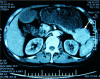

Glucagonoma syndrome is a rare paraneoplastic phenomenon. Necrolytic migratory erythema is often one of the first presenting symptoms. We report a case of a 55-year-old man with a 2-year history of recalcitrant eruption. Abdominal computer tomography was performed, which revealed a tumor in the tail of the pancreas. After pancreatectomy, his cutaneous lesions vanished in a few days. Skin symptoms are important, as they are often essential for early diagnosis of glucagonoma syndrome and may prevent metastatic disease; hence, in this report, we focus on skin disorders in glucagonoma syndrome.